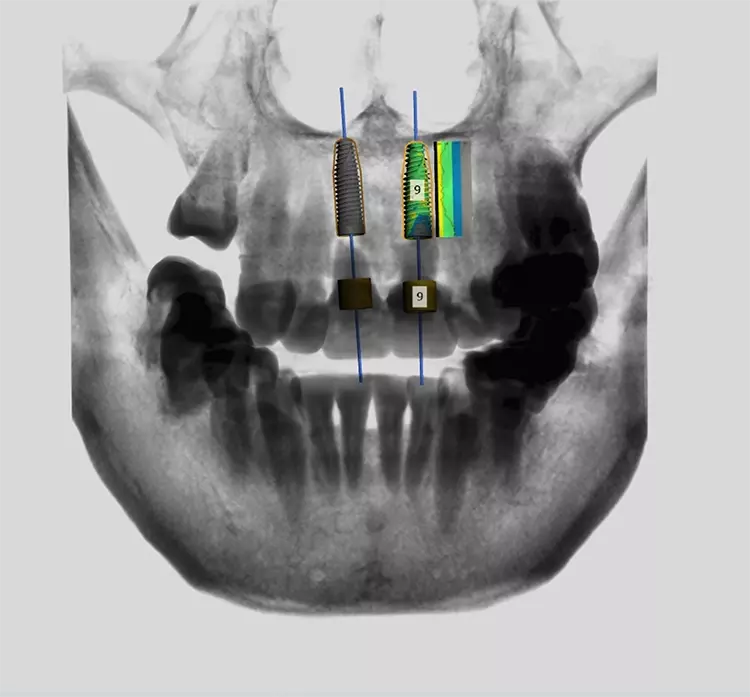

So wurde die Rehabilitation zur Wiederherstellung von okklusaler Stabilität, VDO (Vertikale Dimension der Okklusion) und funktionsorientierten Zahnführungen Schritt für Schritt vorgenommen. Zwischenzeitlich visualisierte der Zahntechniker die vorläufige Implantatplanung für die später folgende navigierte Implantation (Abb. 10). Der chirurgische Eingriff wurde simuliert, indem virtuelle Zähne in der CAD-Planungssoftware (Implant Studio, 3shape) entworfen wurden, wobei die Kontur des Alveolarfortsatzes beibehalten wurde.

Die Bohrschablone wurde additiv aus speziellem 3D-Druckharz (Cosmos SG, Yller) auf einem Photon Mono 4K (Anycubic) hergestellt. Die Zähne wurden atraumatisch unter Erhaltung der Integrität der Gingiva und der Gingivaarchitektur extrahiert (Abb. 11).